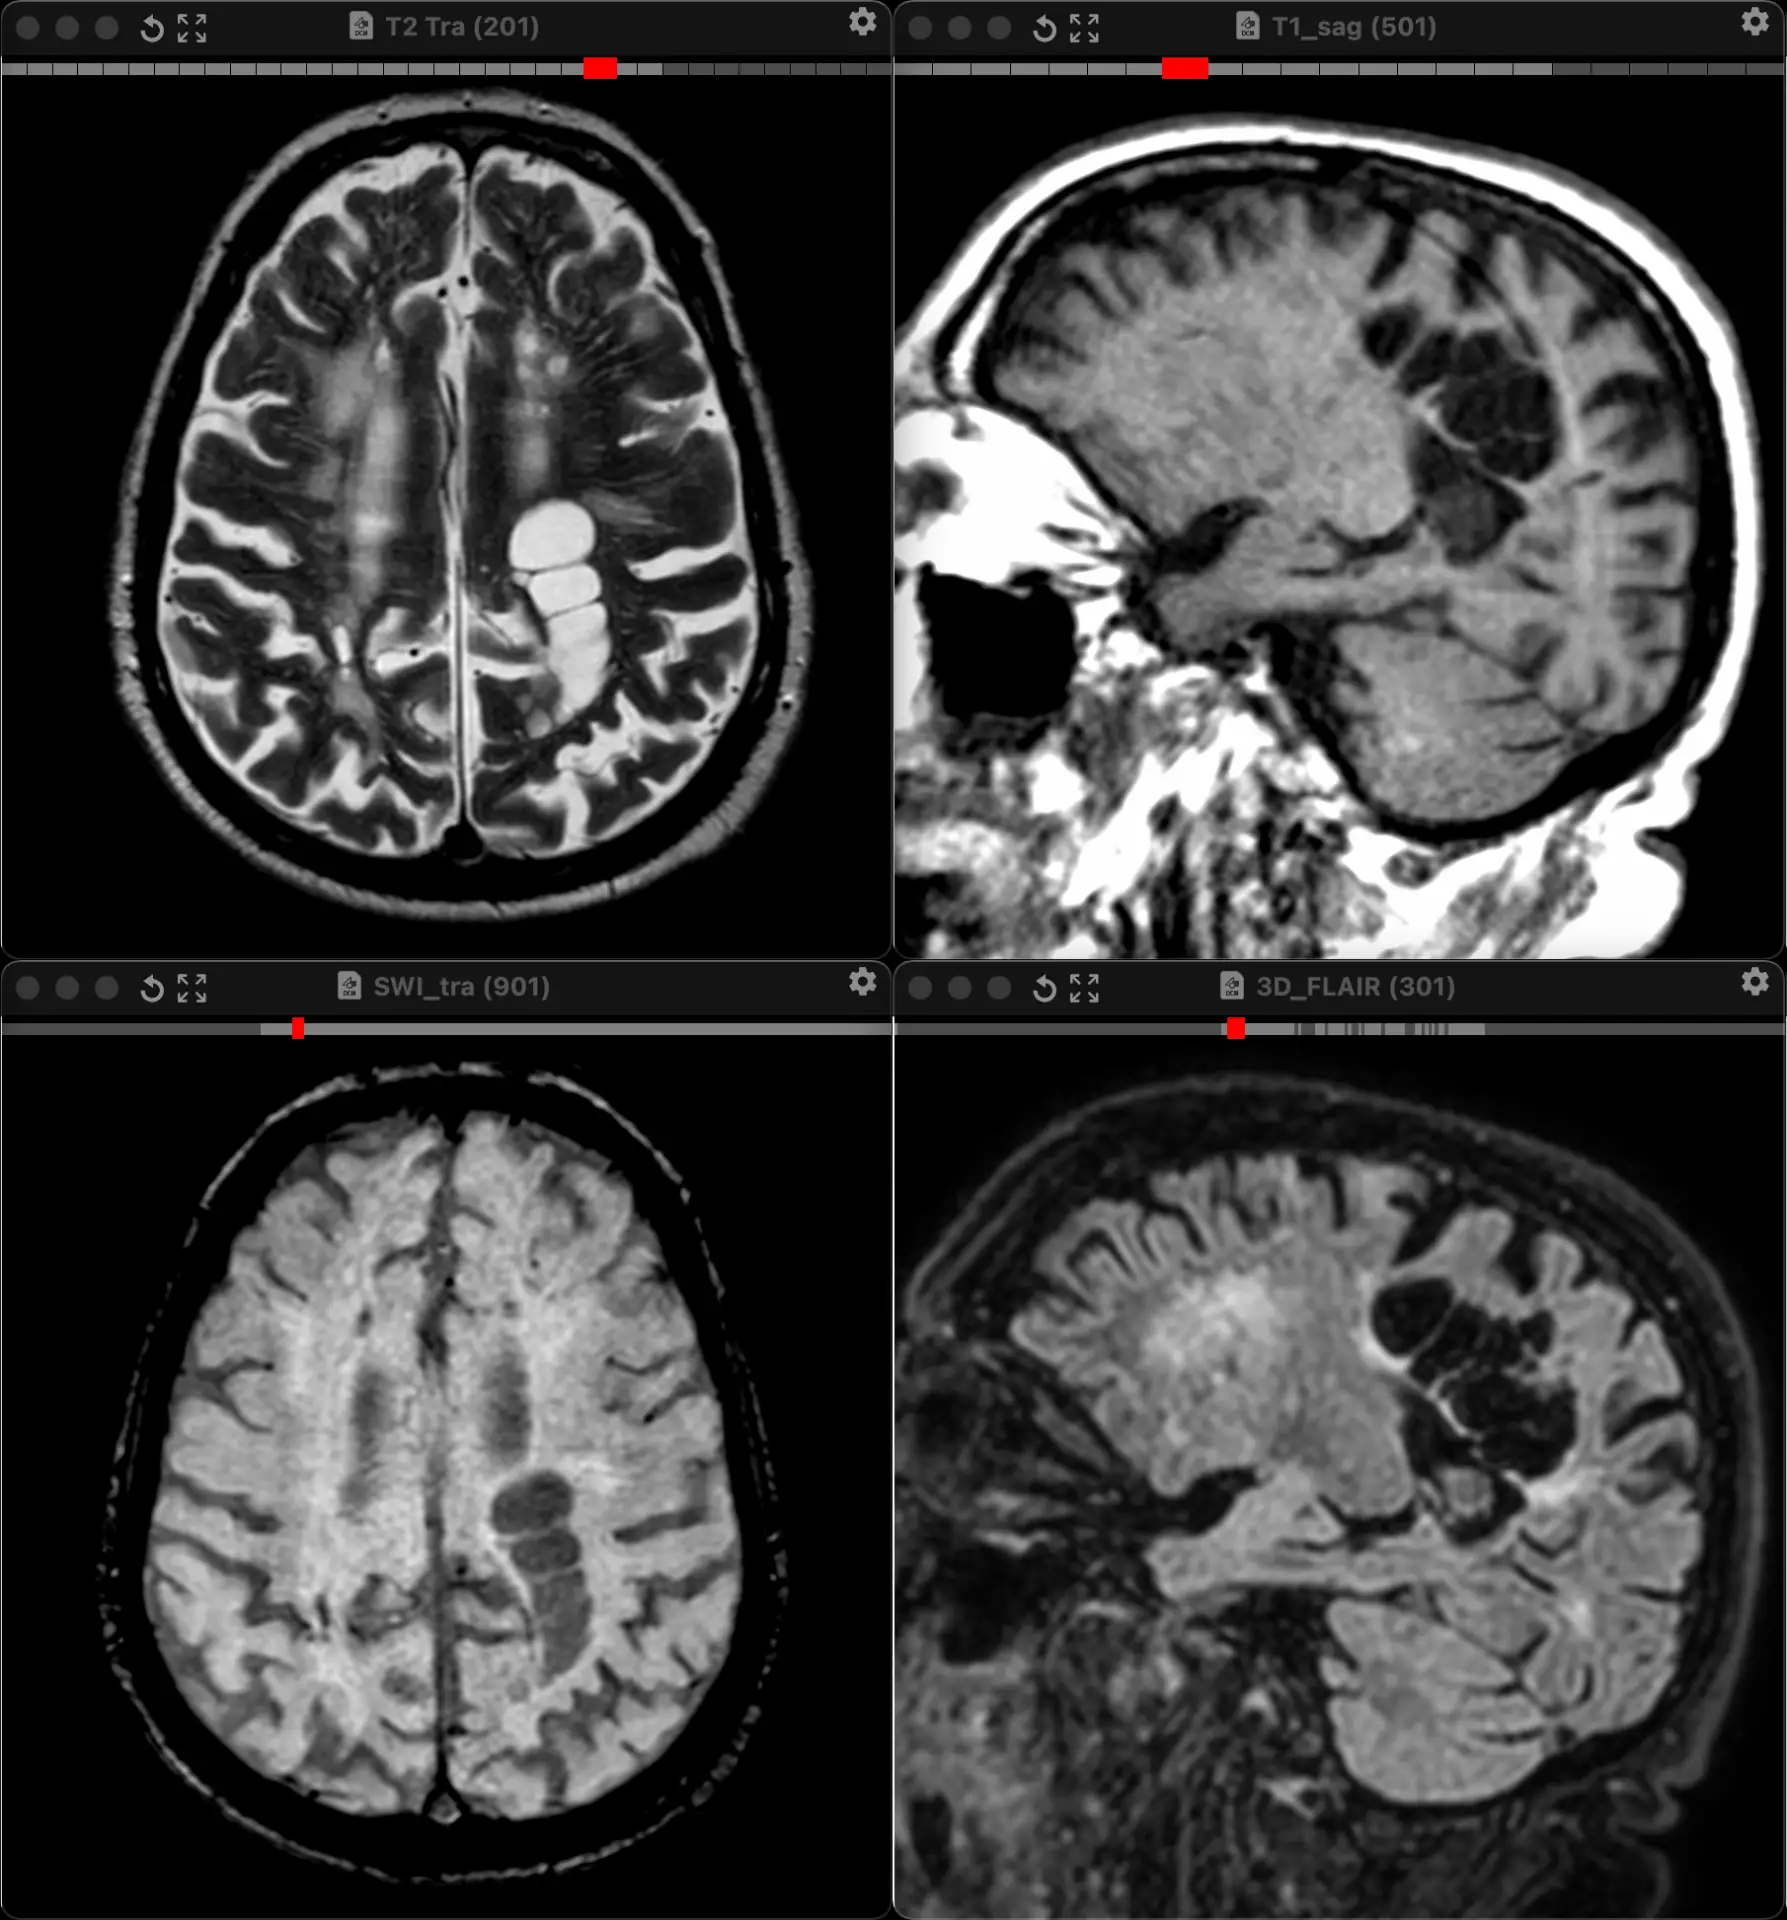

Женщина 32 года. Больной считает себя с 2024 г, когда стала отмечать онемение угла рта. Со слов пациентки ей был предварительно выставлен диагноз - РС, но дополнительных методов обследования и специфического лечения не проводилось. В настоящее время жалоб нет. В исследовании от октября 2024 отмечался очаг в левой затылочной доле с выраженным контрастированием, в настоящее время этот же очаг отмечается с сохраняющимся контрастированием. Формально - есть выполнение критериев диссеминации и в пространстве (юкстакортикальный и перивентрикулярный очаги есть), и во времени (есть усиливающиеся и неусиливающиеся очаги), клиника тоже вполне укладывается. Но! Найти в литературе подобных случаев мне не удалось, видел сам и максимум, что находил в литературе - полгода контрастирования. Получается, мы имеем дело с крайне атипичным рассеянным склерозом, или это не рассеянный склероз. А тогда что? Сосудистая мальформация не вариант - на SWI не видать. Какая-то ганглиоглиома? А другие очаги тогда что? Есть соображения? Кстати, диффузия стойко повышенная, и на б1000 почти не видно (изо). На Т2 не меняется